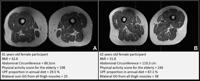

(University of California, San Francisco / Radiology via SWNS)

Akkaya, from the University of California, San Francisco, explained that can be seen via MRI scans as fatty degeneration of the muscle, where streaks of fat replace muscle fibers.

She said: "In addition to investigating the quality of our modern diet in relationship to thigh muscle composition, in this study, we used widely available, non-enhanced MRI, making our approach accessible and practical for routine clinical use and future studies.

"These MRIs do not require advanced or costly technology, which means they can be easily incorporated into standard diagnostic practices."

"This is the first study assessing ultra-processed food's impact on thigh muscle composition using MRI."